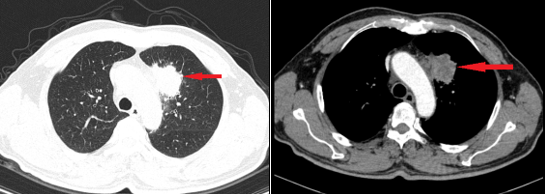

- Chụp cắt lớp vi tính lồng ngực: Hình ảnh khối nhu mô thùy trên phổi trái kích thước 38x38x59 mm, bờ tua gai co kéo gây giãn các nhánh phế quản lân cân, ngấm thuốc mạnh không đều sau tiêm, xâm lấn trung thất. Hạch trung thất dưới carina, dọc quai động mạch chủ và rốn phổi trái, hạch lớn nhất kích thước 14x11 mm.

Hình 2: Hình ảnh cắt lớp vi tính lồng ngực lúc mới: khối thùy trên phổi trái xâm lấn trung thất (mũi tên đỏ).